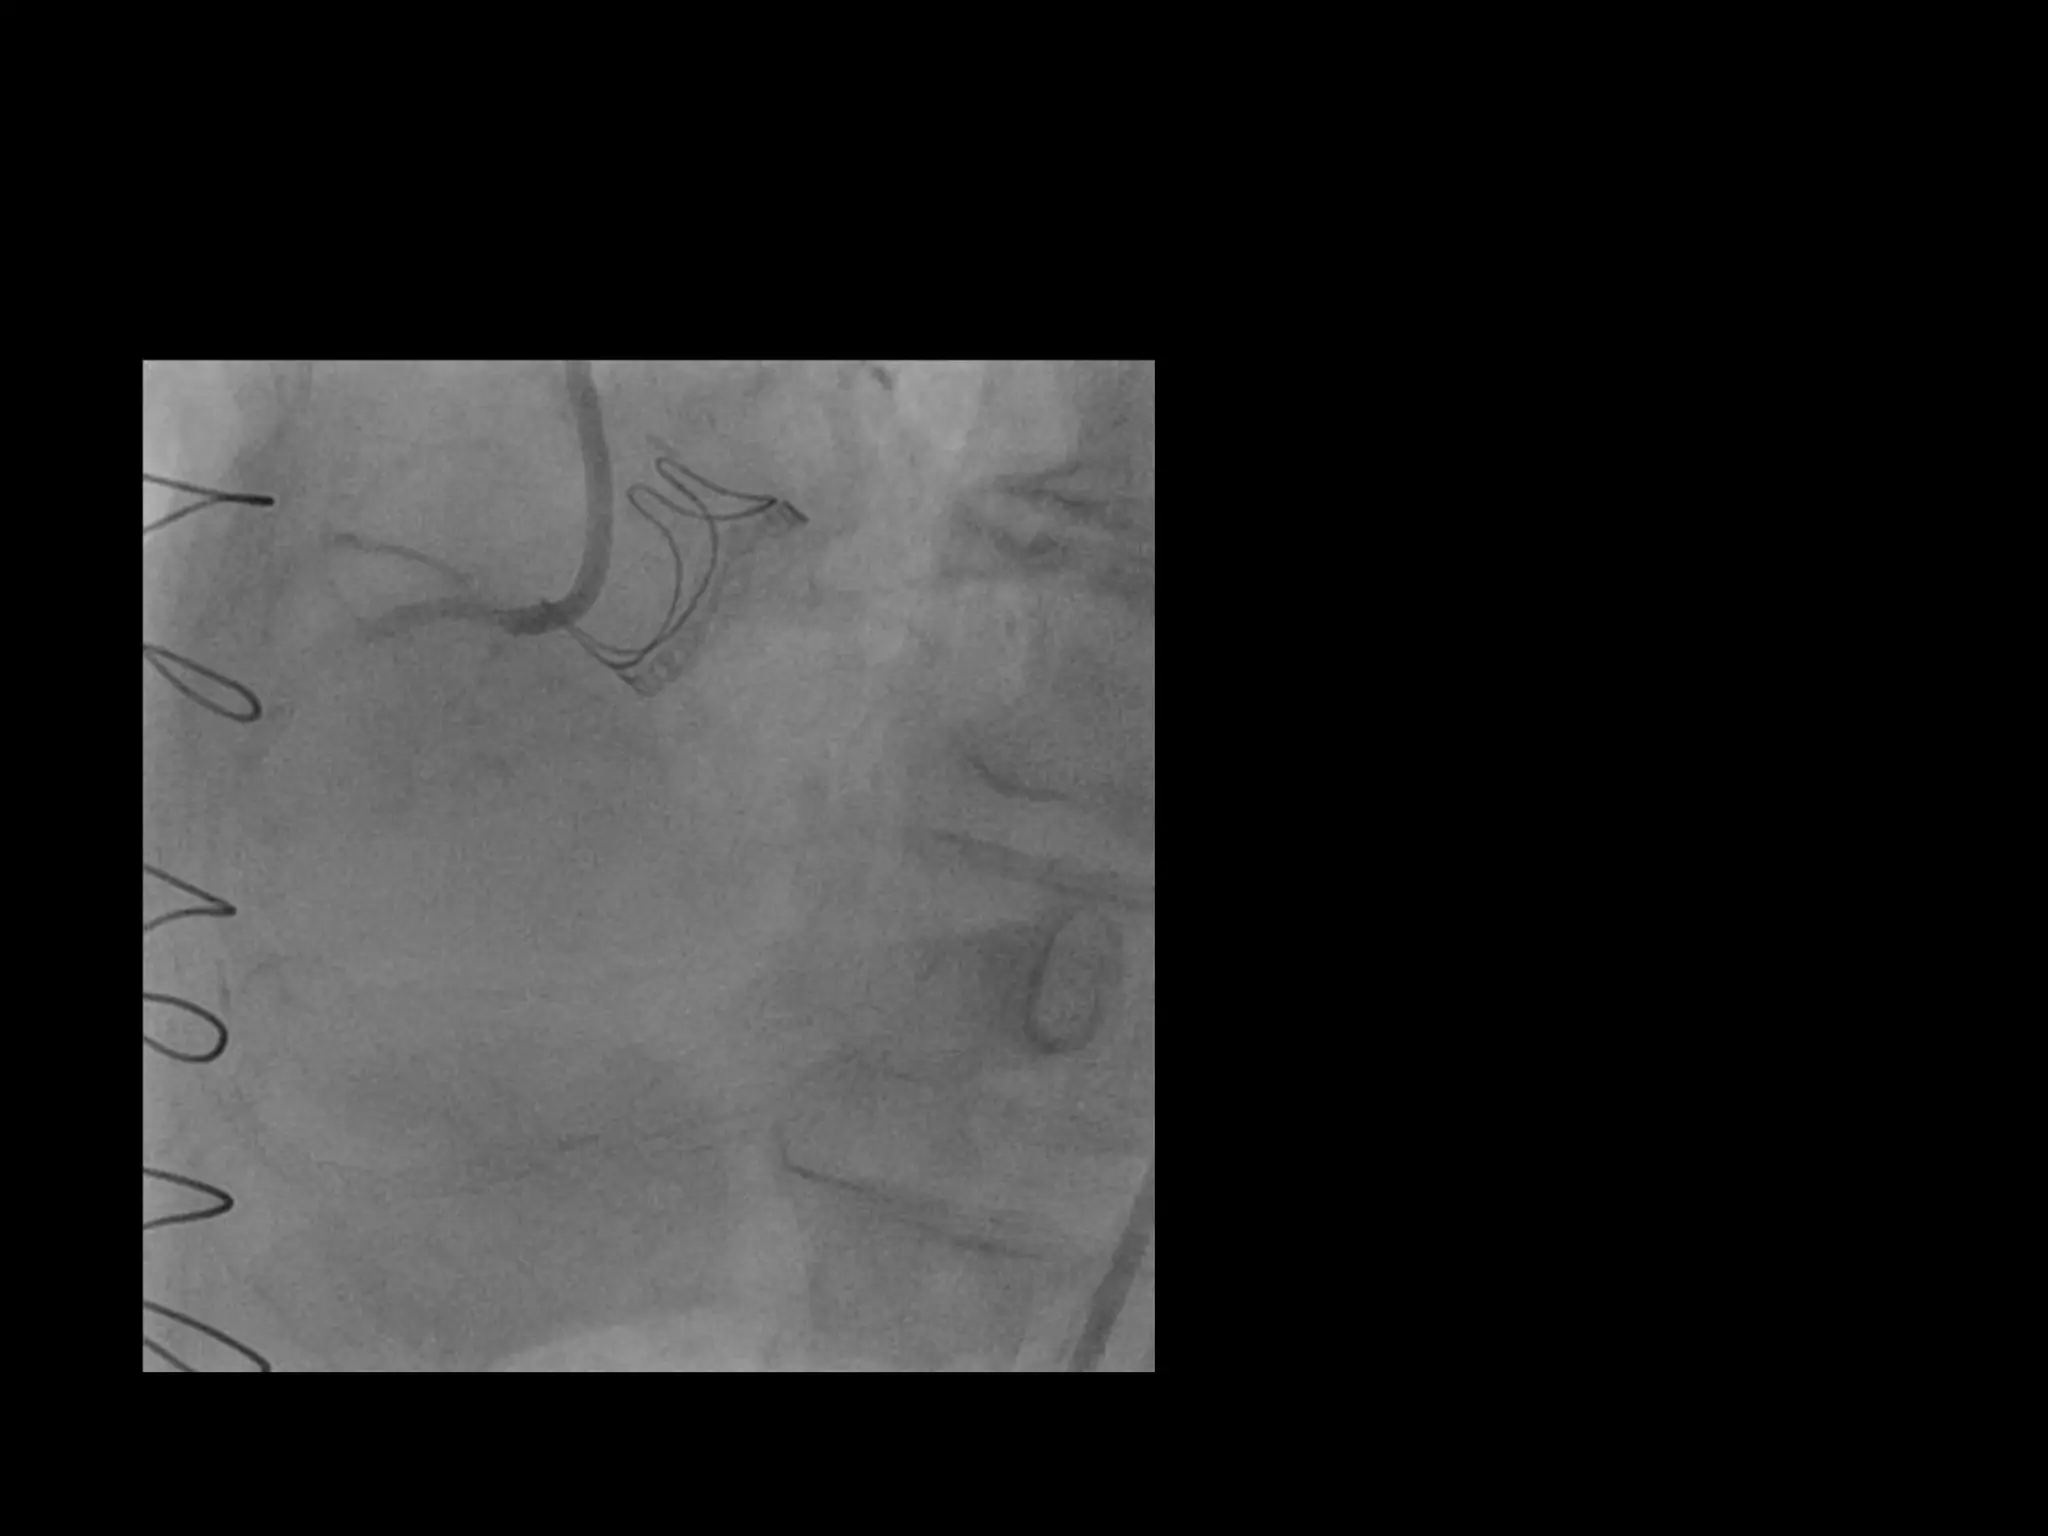

This document provides guidance on evaluating the feasibility of percutaneous coronary intervention (PCI) for a chronic total occlusion (CTO). Key factors to consider include: the patient's tolerance for a long procedure, contrast load, and radiation exposure; the CTO's proximal cap ambiguity, length, distal landing zone, and presence of interventional collaterals; and ensuring good quality angiography. With adequate planning and use of appropriate CTO techniques, feasibility is nearly always present for symptomatic patients. Success rates of CTO-PCI are reported to be 94% when using a planned approach.